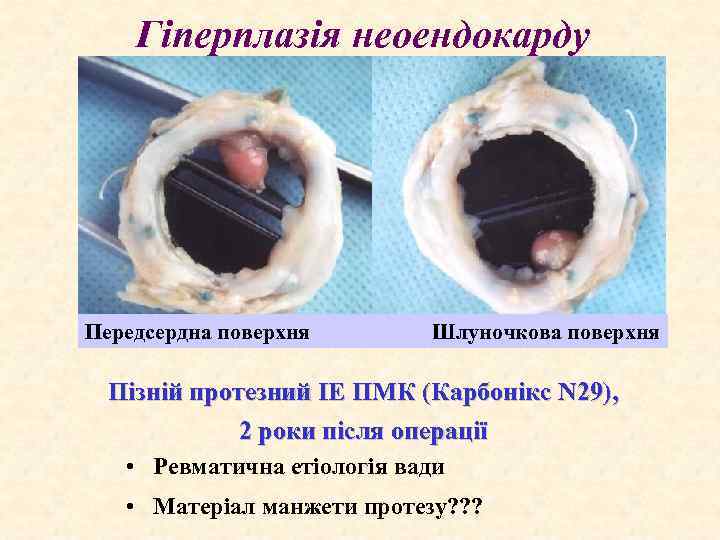

Гіперплазія неоендокарду Передсердна поверхня Шлуночкова поверхня Пізній протезний ІЕ ПМК (Карбонікс N 29), 2 роки після операції • Ревматична етіологія вади • Матеріал манжети протезу? ? ?